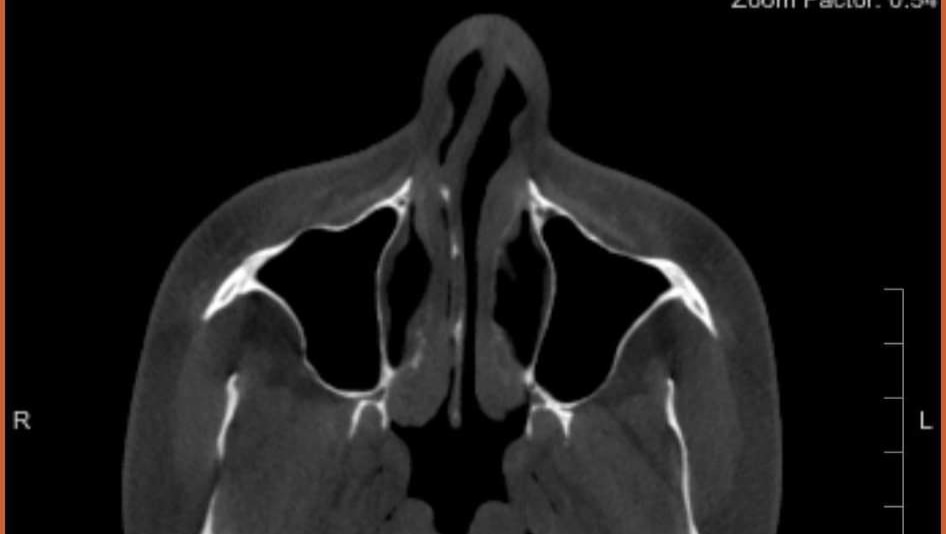

After assessing everything, Dr. Hamilton stated that Kinslee was in immediate need of septal repair. He informed us that the buttons that had been in place over the last few months had done nothing but damage the septal area even further. He added that a septal button should never be placed in any hole or perforation over 2 cm and during his initial scans and measurements found there were numerous areas of Kinslee's perforated septum that measured as big as 4 cm. He informed us that no matter how we decided to proceed, that the first thing that needed to happen was for the septal button to be removed immediately. An hour later, after what we thought would be a 10-minute consultation, Kinslee was being prepped for a procedure right there in the office in order to remove the septal button. Once the doctor removed the septal button, he did another scan and assessed the situation under camera even more extensively and told us that what we needed was just shy of a miracle. It appears that Kinslee has no cartilage left in her nose and that some would need to be taken from her ribs in order to build a new septum. At this point, Dr. Hamilton is the only doctor that has agreed to take on our case, stating that it is going to be a lot of work and may require more than 1 surgery. There was 2 hurdles standing in our way. The first being that Hamilton's surgery calendar was currently booked out through September. Working in our favor was the fact that we needed immediate action on something that should have been addressed months ago. We left that afternoon with some good answers and a lot of info, but unsure of the next steps.